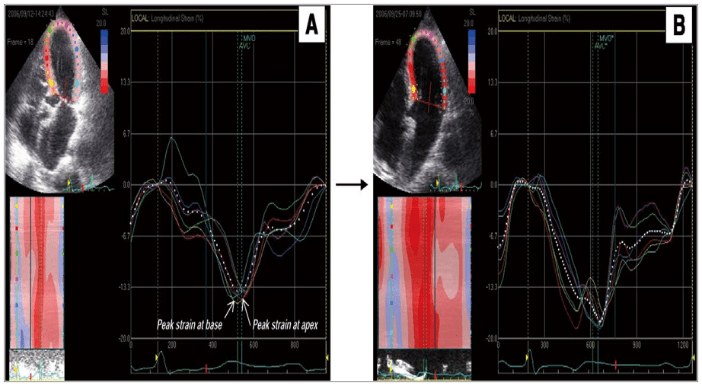

Добутамин эхо

Добутамин эхо 116 фото